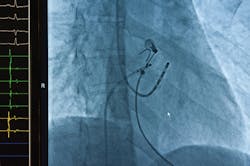

CHICAGO, IL – Marker bands are small metal bands attached to catheters for minimally invasive medical procedures. The bands are radio-opaque (highly visible under x-ray), giving physicians much-needed visibility of the catheter location during procedures (FIGURE).